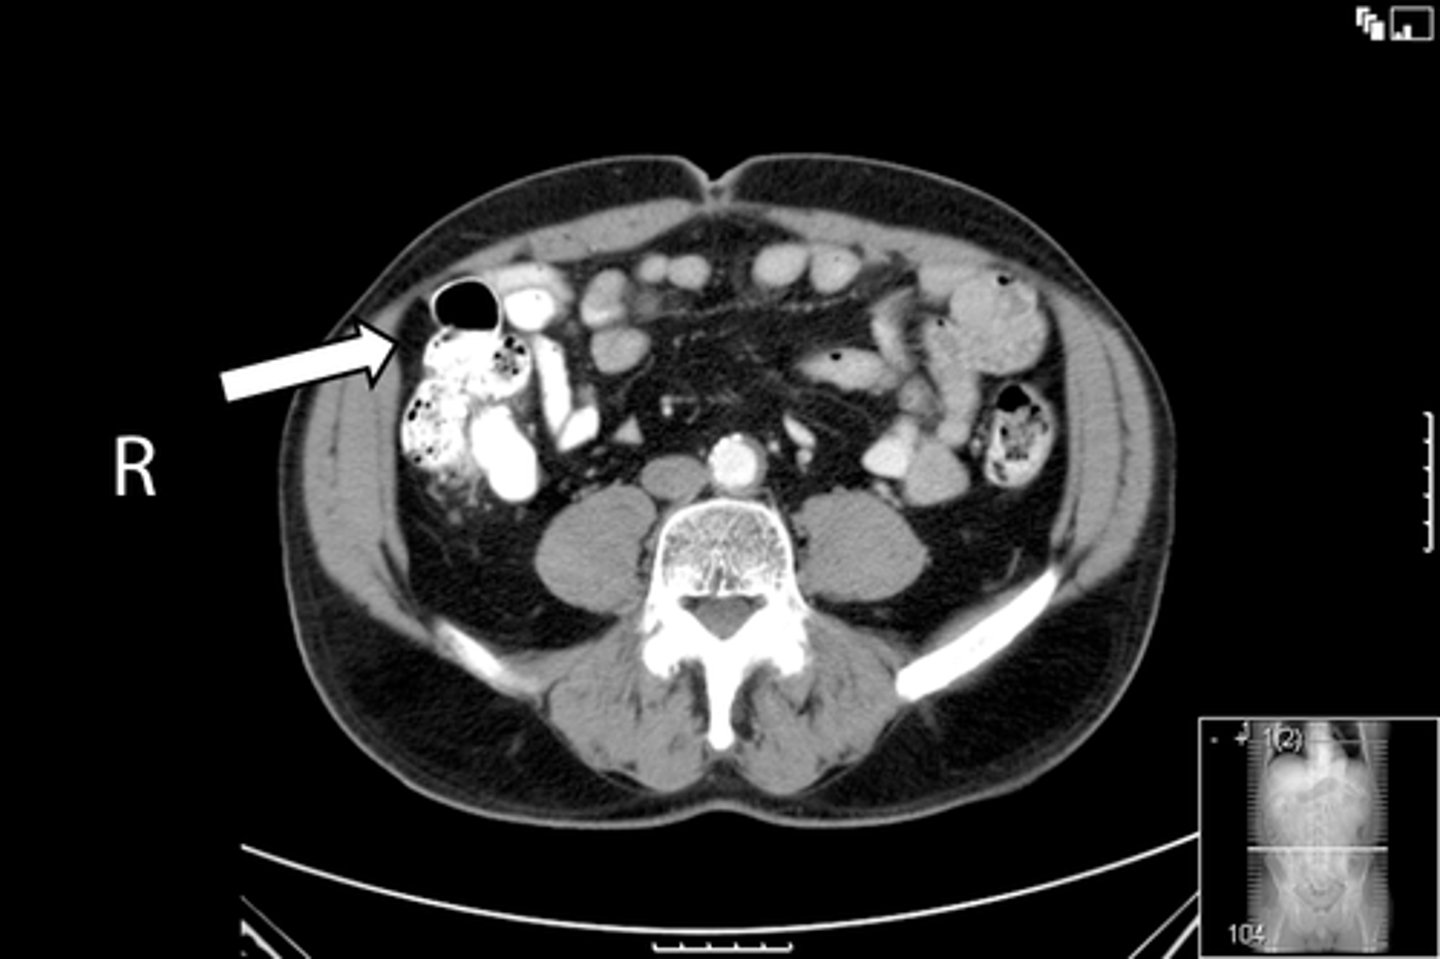

37

New cards

Axial bony pelvis CT

What is the image?

<p>What is the image?</p>

38

L acetabulum

What is indicated in the image?

<p>What is indicated in the image?</p>

39

L femoral head

40

L piriformis muscle

41

R femoral head

42

R piriformis muscle

43

R acetabulum (posterior part)

44

Sacrum